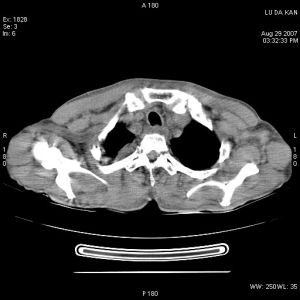

可發現肺部原發病灶、縱隔增寬或肺門淋巴結增大。胸部CT或MRI檢查

有助於明確上腔靜脈阻塞的原因。其他